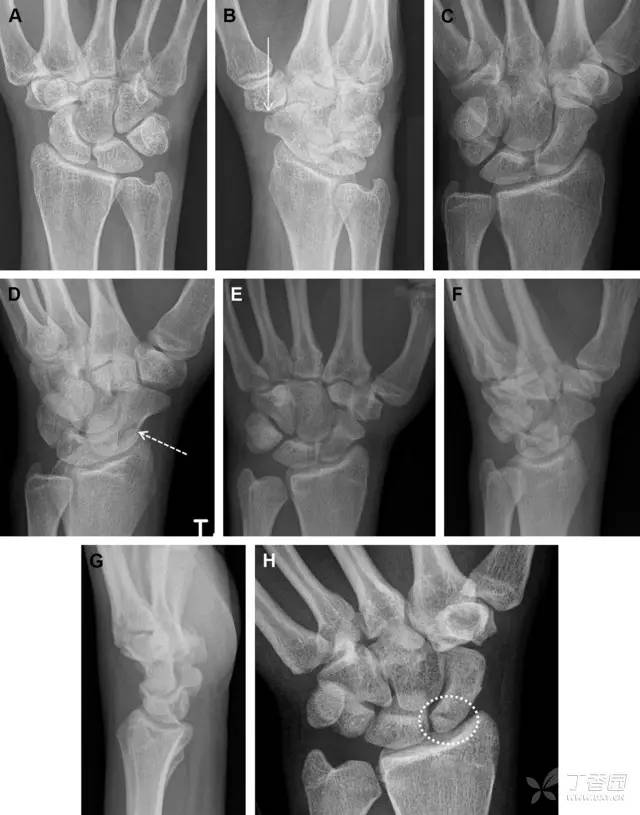

31 舟状骨骨折

舟状骨骨折 60%~70% 发生于腰部,15% 发生于近极, 10% 发生于远极, 8% 发生于远端关节面。除了常规的前后位、侧位、斜位片外,还需要拍专门的舟状骨位片(腕关节尺偏,以舟状骨为中心的腕关节前后位片),特别是鼻烟壶有压痛时。

图 2 舟状骨骨折 (A、B)第 1 例患者,舟状骨远极关节内骨折(白色箭头),斜位片显示较清楚(B);(C、D)第 2 例患者,舟状骨腰部骨折(虚线箭头),斜位片显示较清楚(D);(E~H)第 3 例患者,舟状骨近极骨折,常规 X 线片均未看到骨折,而在舟状骨位片上才能见到骨折(虚线圆)